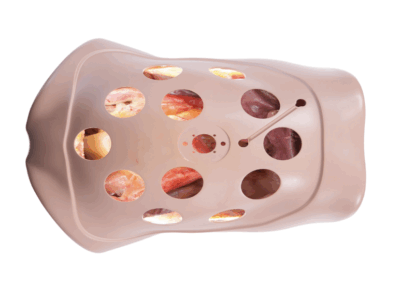

Modelos

Anatômicos

Ferramentas para estudo detalhado do corpo humano.